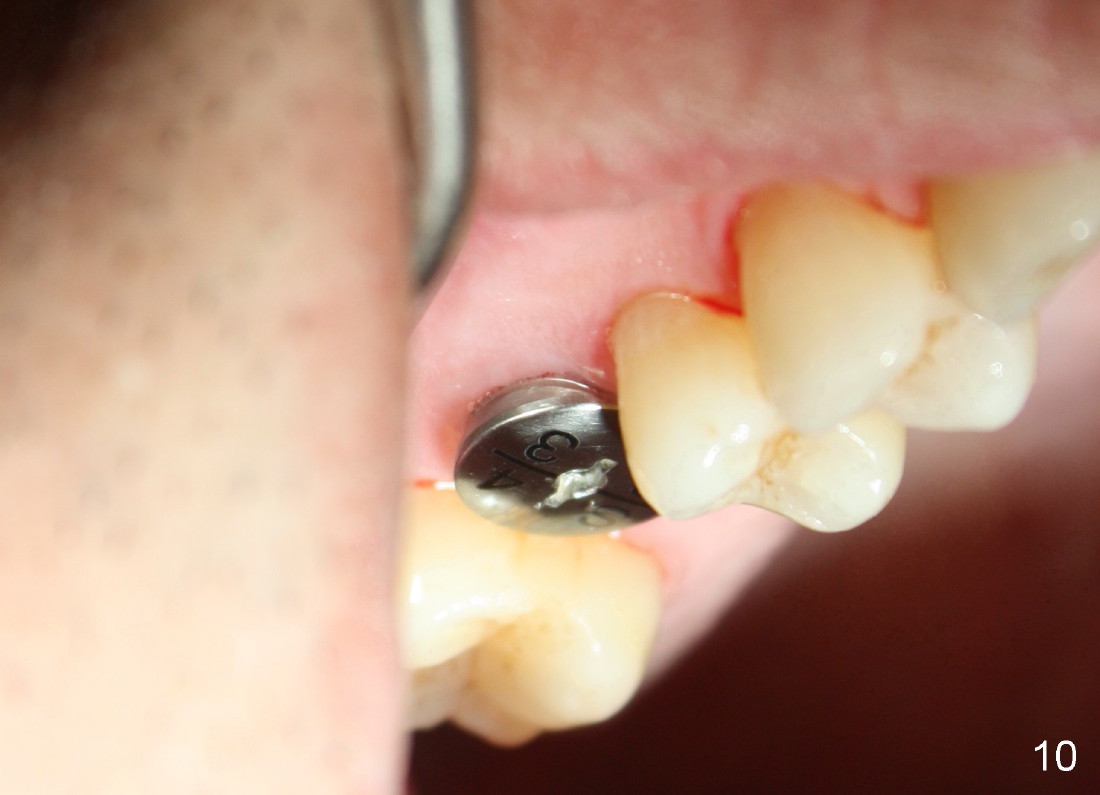

The tooth #3 has a crack line (Fig.1 ^). The septum (Fig.2 S) looks like an inverted pyramid (Fig.3), coronal part being pointed, whereas the apical broad. The shape of the septum is not so favorable to placement of tapered implant. Osteotomy starts with 1.5 mm pilot drill in the middle of the septum, followed by round tapered osteotomes 2 and 3 mm. The osteotomy begins to deviate into the mesiobuccal socket. The same osteotomes are used to re-direct the osteotomy palatally, followed by tapered drills, trying to move osteotomy palatally. A 4.5x17 mm tap is inserted with stability (Fig.4). Following using 5x17 mm tap at the depth of 12 mm, a 5.3x12 mm bone-level implant is placed ~ 1.5 mm below the crest, 1.5 mm above the septum (Fig.5). Demineralized cortical human allograft is placed in the remaining sockets and around the most coronal aspect of the implant (with a small piece of gauze placed in the implant well). After removal of the gauze, a piece of collagen membrane is pierced and carried by a 8.2x4/3 mm healing abutment and fixed in place (Fig.6 M). The periphery of the membrane is tucked underneath the gingiva. The wound is covered by perio dressing. The patient returns to clinic for follow up 8 days postop. There is no discomfort. In order to protect the collagen membrane (Fig.6), the perio dressing is intentionally not removed (Fig.7). Two weeks postop, the patient remains asymptomatic. After perio dressing removal, the membrane appears to have been resorbed (Fig.8 as compared to Fig.6). The bone graft (B), although exposed, remains in place and condensed, surrounded by healing healthy gingiva (*). The patient returns 2.5 months postop. The implant appears to osteointegrate (Fig.9, as compared to Fig.5). The buccal (Fig.10) and palatal (Fig.11) gingiva adapts to the healing abutment. When the healing abutment is removed for restoration 3 months postop, the gingiva looks healthy (Fig.12). A cemented abutment (5.8x4(2) mm) is placed; a crown is fabricated (Fig.13). The patient returns for recall 5 months post cementation. He reports food impaction distal to the crown. The gap mesial to the implant has closed (Fig.14).